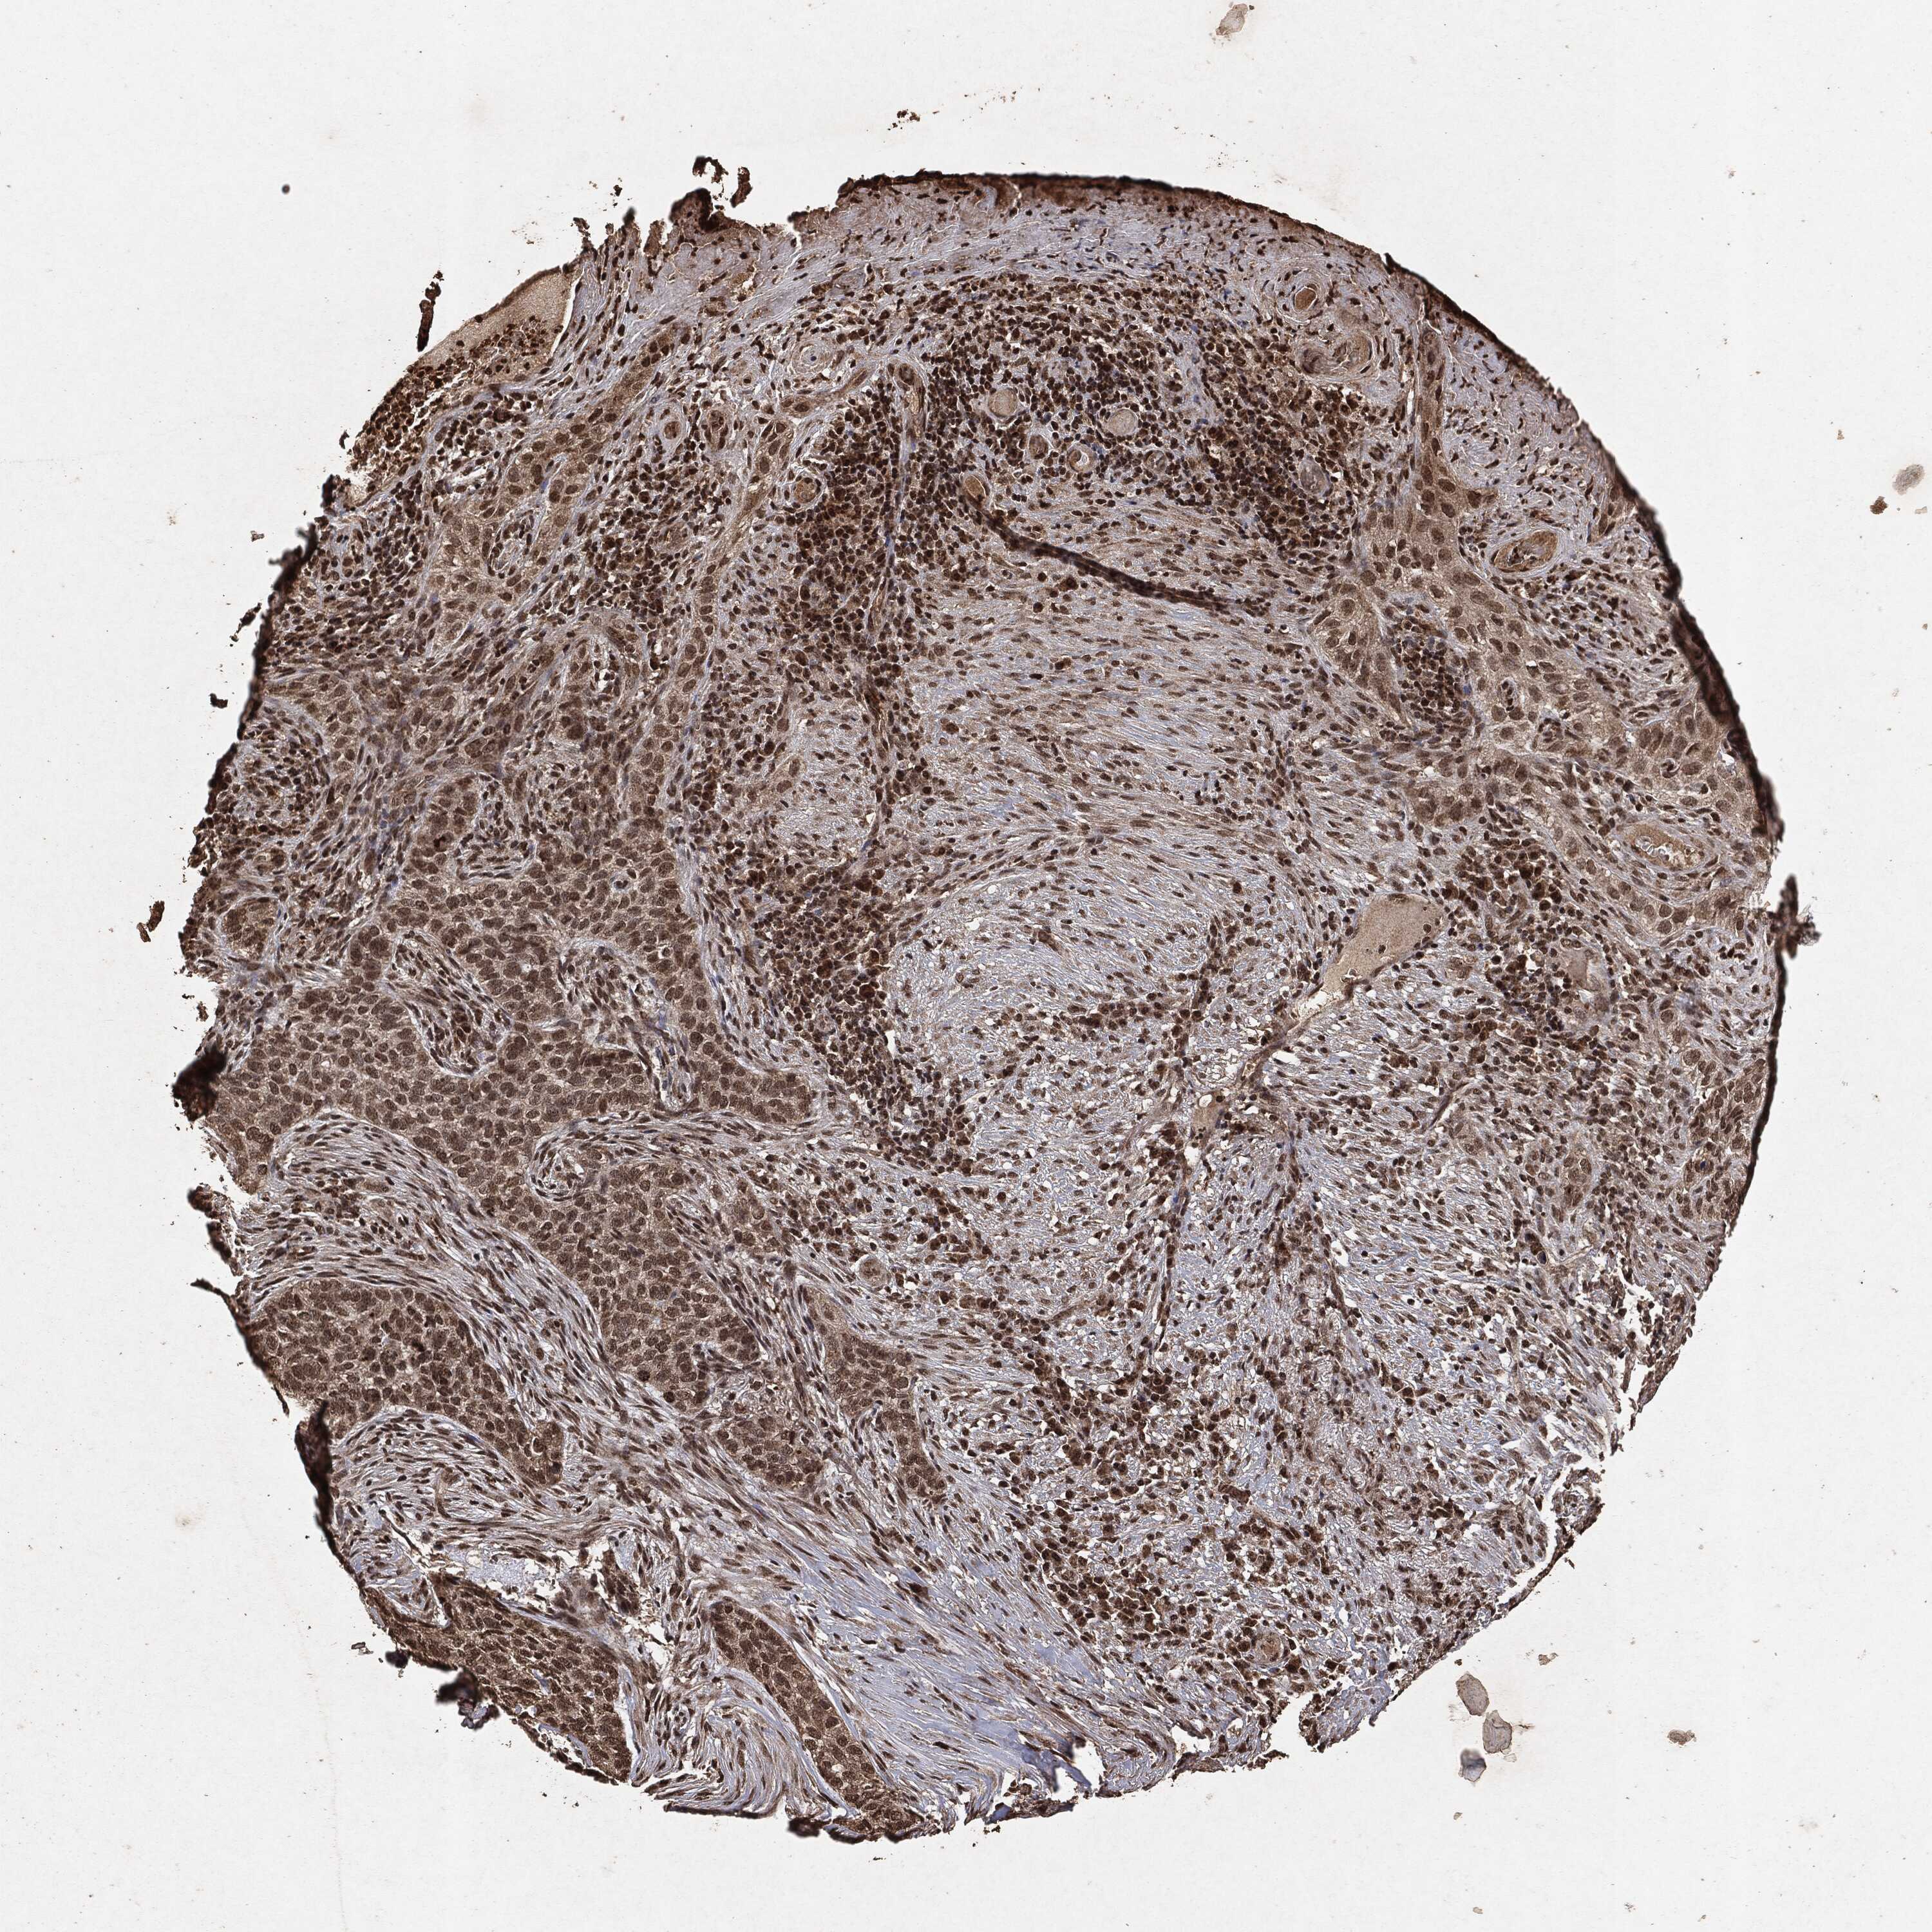

SKIN CANCER - Protein expressioni

A mouse-over function shows sample information and annotation data. Click on an image to view it in a full screen mode. Samples can be filtered based on level of antibody staining by selecting one or several of the following categories: high, medium, low and not detected. The assay and annotation is described here.

Antibody staining in the annotated cell types in the current human tissue is reported as not detected, low, medium, or high, based on conventional immunohistochemistry profiling in selected tissues. This score is based on the combination of the staining intensity and fraction of stained cells.

Each image is clickable and will lead to virtual microscopy that enables deeper exploration of all samples and also displays staining intensity scores, fraction scores and subcellular localization as well as patient and tissue information for each sample.

Squamous cell carcinoma, NOS

Basal cell carcinoma

Squamous cell carcinoma in situ, NOS

Squamous cell carcinoma, metastatic, NOS